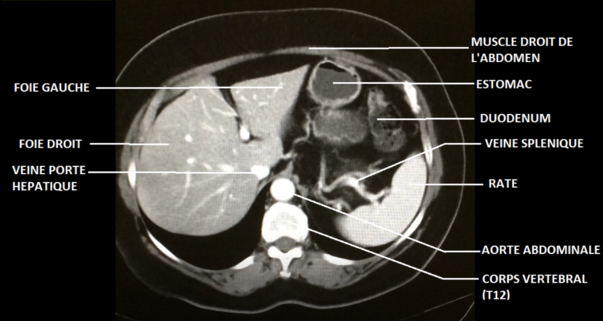

Sur ta coupe, le corps de la

vertèbre serait quant à lui plutôt carré, avec ses deux processus transverses latéraux et son unique processus épineux postérieur. Je t'ai joint ci-dessous le schéma de l'an dernier sur lequel figure le rachis

- coupe axiale abdomen.png (122.43 Kio) Consulté 4243 fois